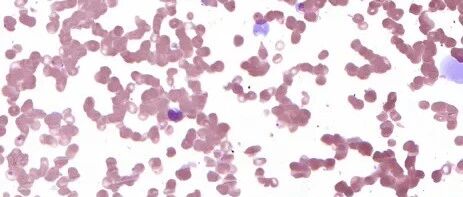

提供检验医学细胞形态交流平台,帮助各级医院的医学检验专业人员更好的了解、学习细胞形态及血液病MICM综合诊断。